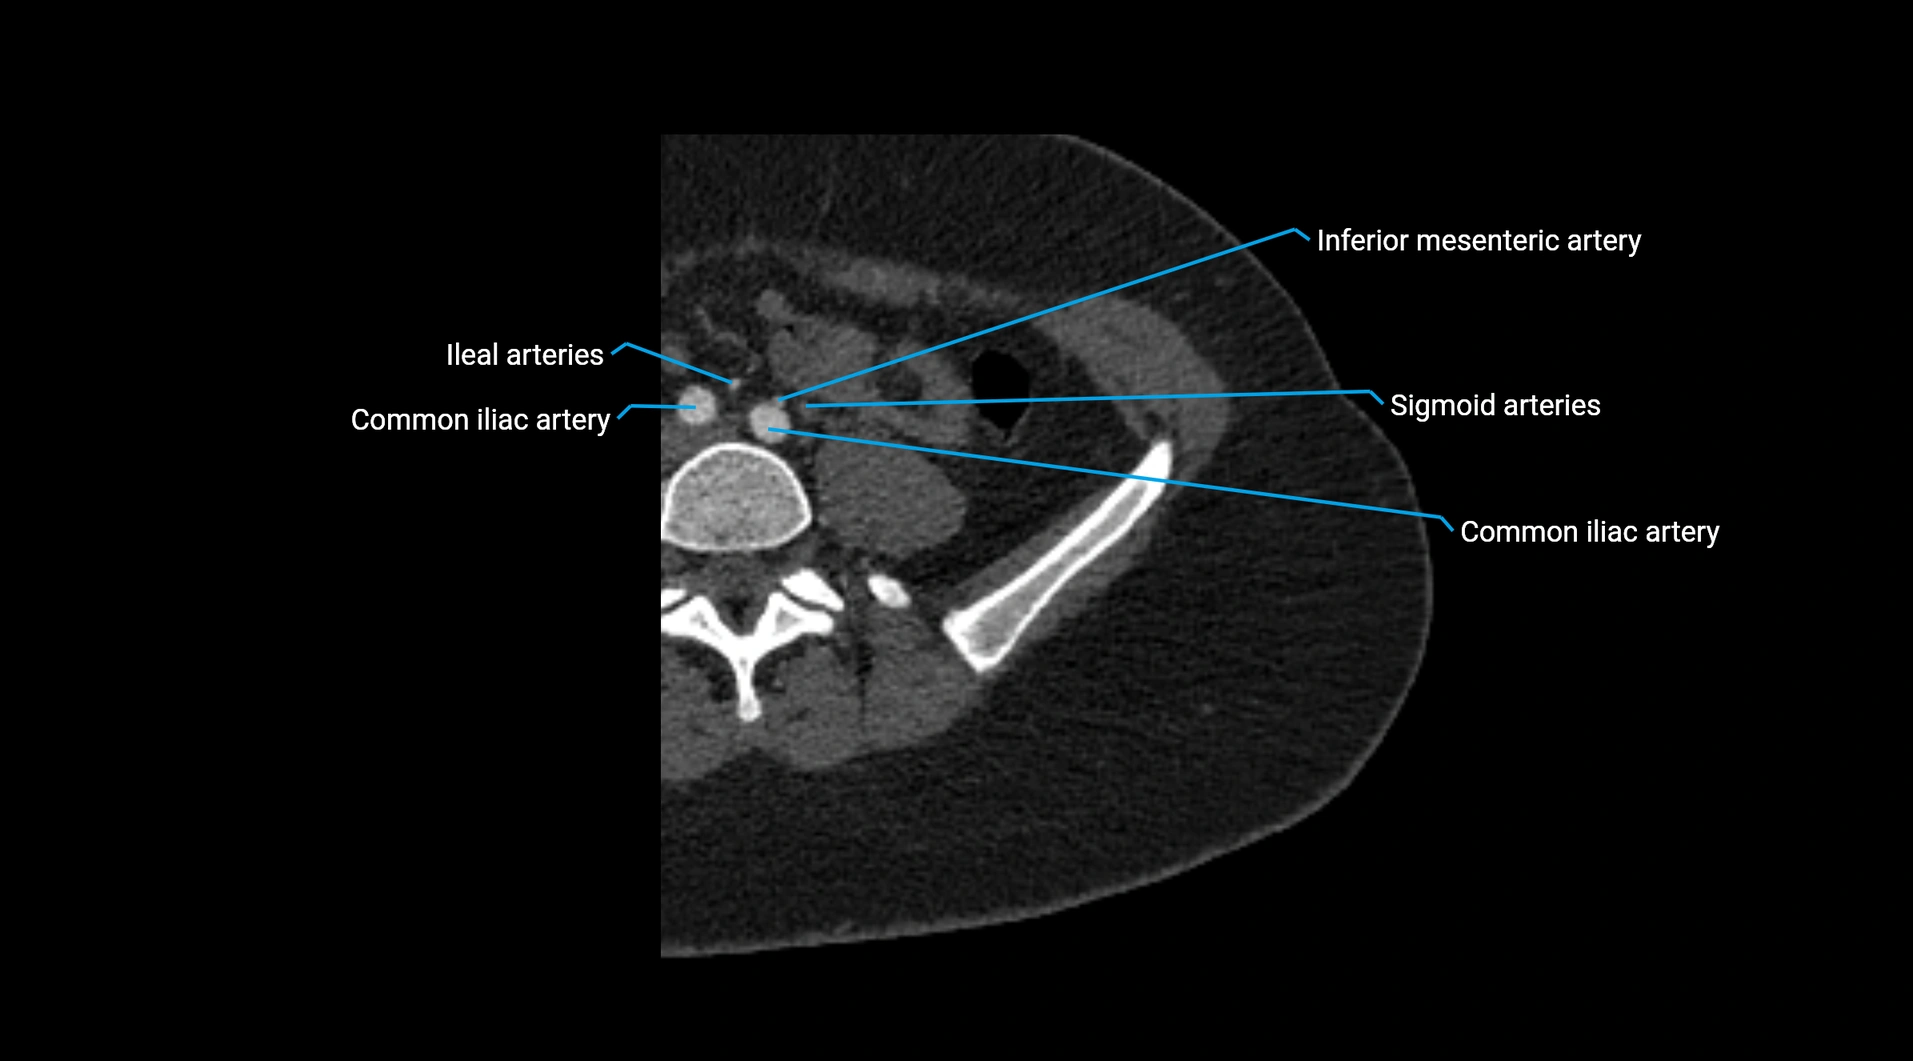

CT images

image